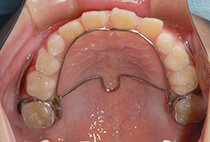

治療は、急速拡大+前方けん引装置から。

成長に合わせて3回の急速拡大を行い、夜間のマウスピースとお口の機能訓練で成長をサポート。小学生を正常なバランスで過ごすことができました。

小児矯正、急速拡大装置、上顎前方けん引

治療は、急速拡大+前方牽引装置から。

成長に合わせて3回の急速拡大を行い、夜間のマウスピースとお口の機能訓練で成長をサポート。